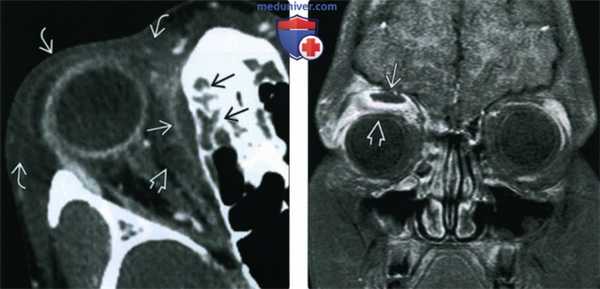

(Слева) При аксиальной КТ с КУ над глазничной пластинкой визуализируется поднадкостничный абсцесс, накапливающий контраст в виде «ободка»: пневматизация ячеек решетчатой кости снижена. Обратите внимание на распространенный интракональный отек/тяжистость, проптоз, диффузный пресептальный отек у пациента с синуситом, осложненным орбитальным и пресептальным целлюлитом.

(Справа) При корональной МРТ Т1 ВИ С+ FS у пациента с фронтитом и этмоидитом, осложненным абсцессом экстраконального пространства, определяется смещение глазного яблока вследствие объемного воздействия.